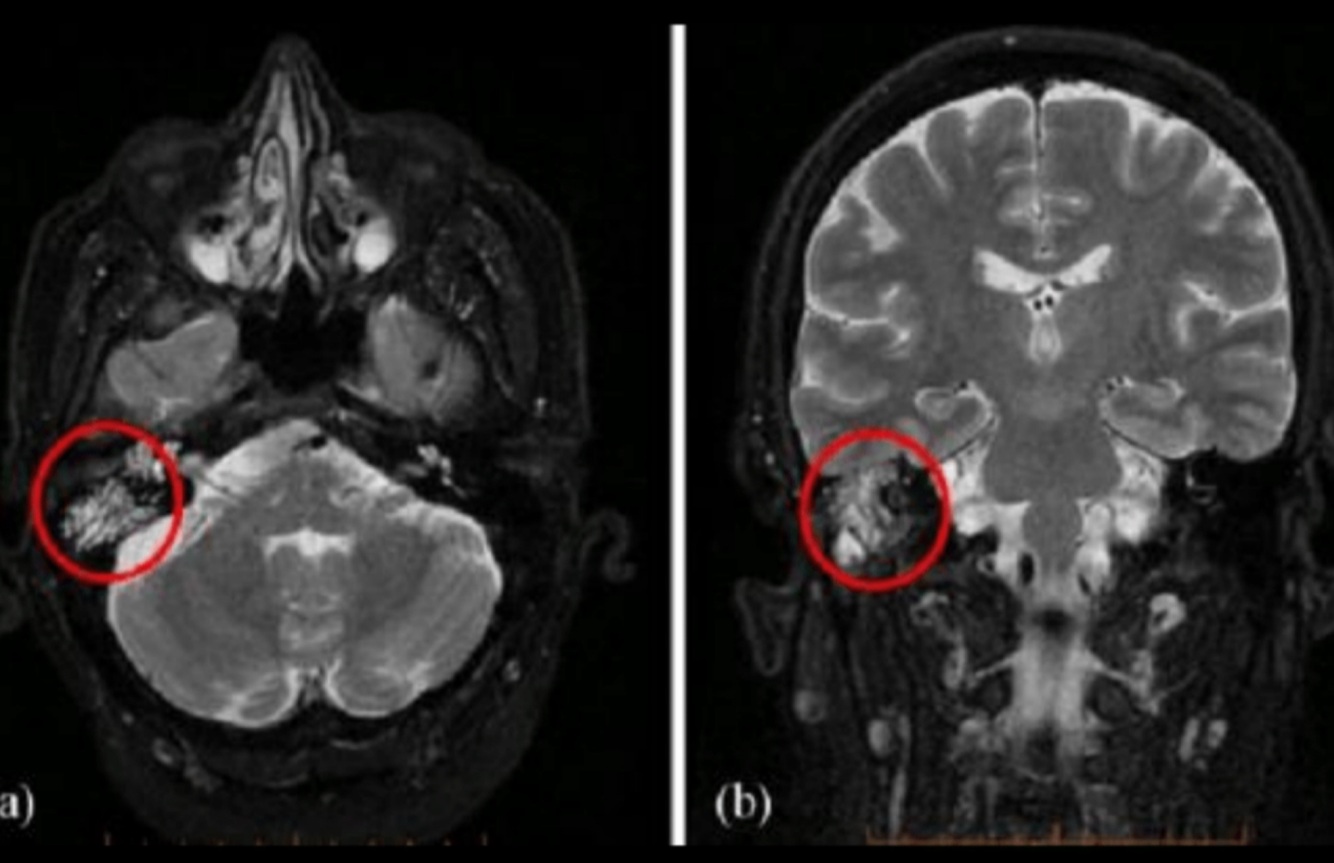

¿Para qué se usa la MRI?

Extensión intracraneal

➞Meningitis

➞Abscesos por complicación

Hallazgos de T2 en mastoiditis complicada:

• Señal aumentada

• Disminución de señal en seno sigmoideo

• Capta contraste